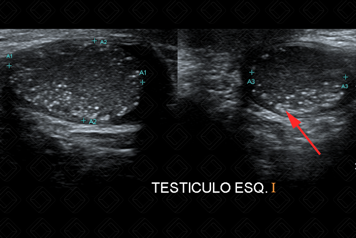

Texto alternativo para a imagem Figuras 1 e 2. Créditos: Dra. Elazir Mota - Rio de Janeiro/RJ

Descrição das figuras 1 e 2: Ultrassonografia de bolsa escrotal. Focos ecogênicos puntiformes, sem sombra acústica posterior, dispersos pelo parênquima testicular bilateralmente, compatível com microlitíase testicular (setas vermelhas).

Exame de imagem: O exame de escolha permanece sendo a ultrassonografia de bolsa escrotal. Na ultrassonografia, observamos focos hiperecoicos difusos pelo parênquima testicular, podendo apresentar ou não sombra acústica posterior. Na maioria dos casos, sua distribuição é bilateral e difusa pelo parênquima. No entanto, seu acometimento pode ser unilateral e focal (figuras acima).

Para ser considerada microlitíase testicular, devem existir cinco ou mais focos hiperecogênicos dispersos pelo parênquima testicular.